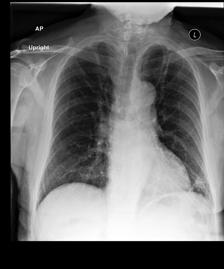

Radiology report generation. As motivated in §1, we apply our method to chest X-ray radiology report generation using the MIMIC-CXR (Johnson et al., 2019) dataset. For our LM, we fine-tune an encoder-decoder architecture based on a pretrained ViT (Dosovitskiy et al., 2021) image encoder and a GPT2-small (Radford et al., 2019) text decoder. To judge admission, we use the popular Clinical Efficacy metric (Liu et al., 2019; Nicolson et al., 2022) to check if the 14 labels predicted by an auxiliary CheXbert (Smit et al., 2020) model on the generated report exactly match the labels predicted by the same CheXbert model for a reference report from a radiologist. Similarly, a component (here a sentence including a finding) is defined to be admissible if it has a ROUGE-L Lin (2004) score 0.4absent0.4\geq 0.4≥ 0.4 (picked empirically), when compared to any component directly extracted from the reference.